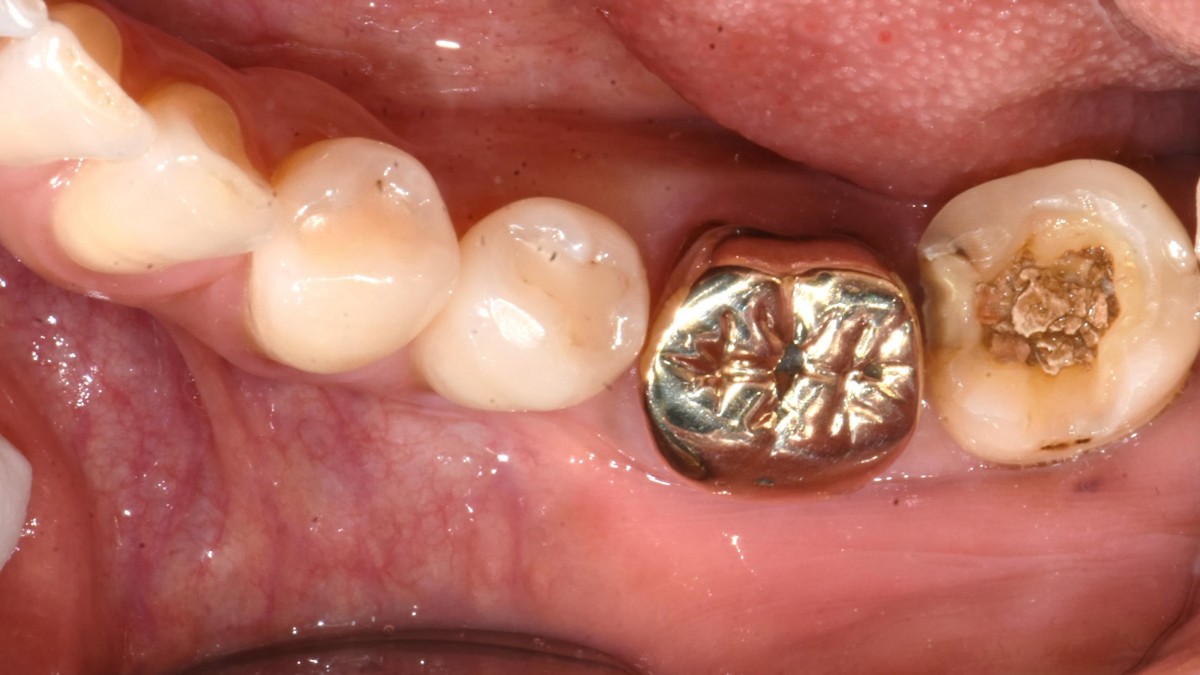

A 51-year-old patient complained of an

old-crowned molar. The lower left molar had a gold crown, and the margin showed discoloration indicative of inner caries. Also, it had furcation-involved periodontitis

Extraction and immediate placement of an implant.